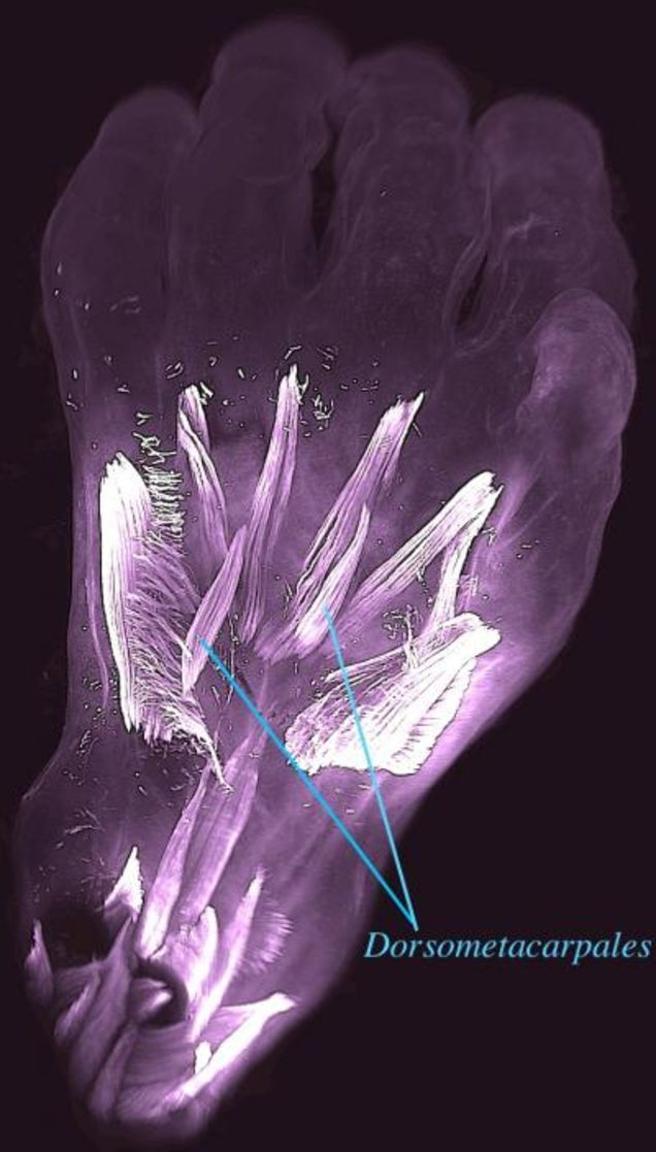

O nouă descoperire științifică! Fetușii umani dezvoltă mușchi de reptile care dispar la naștere Mușchii dorsometacarpali se formează în timpul dezvoltării timpurii (Universitatea Howard). Sursa foto:lavanguardia.com

Unii dintre acești mușchi, cum ar fi dorsometacarpialul, se formează în timpul dezvoltării timpurii și se știe că sunt prezenți la multe animale cu membre.

Experții au stabilit că din 30 de mușchi, de la nivelul mâinilor și picioarelor, formați în jurul săptămânii a șaptea de gestație, o treime se contopesc sau dipar complet în jurul săptămânii 13. Această scădere este drastică și paralelă cu ce s-a întâmplat la nivel evolutiv.